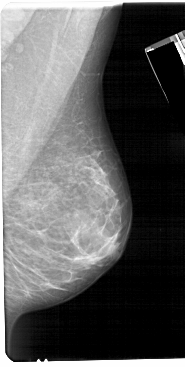

A_1673_1.RIGHT_CC

RIGHT_CC LINES 5206 PIXELS_PER_LINE 2686 BITS_PER_PIXEL 12 RESOLUTION 43.5 NON_OVERLAY